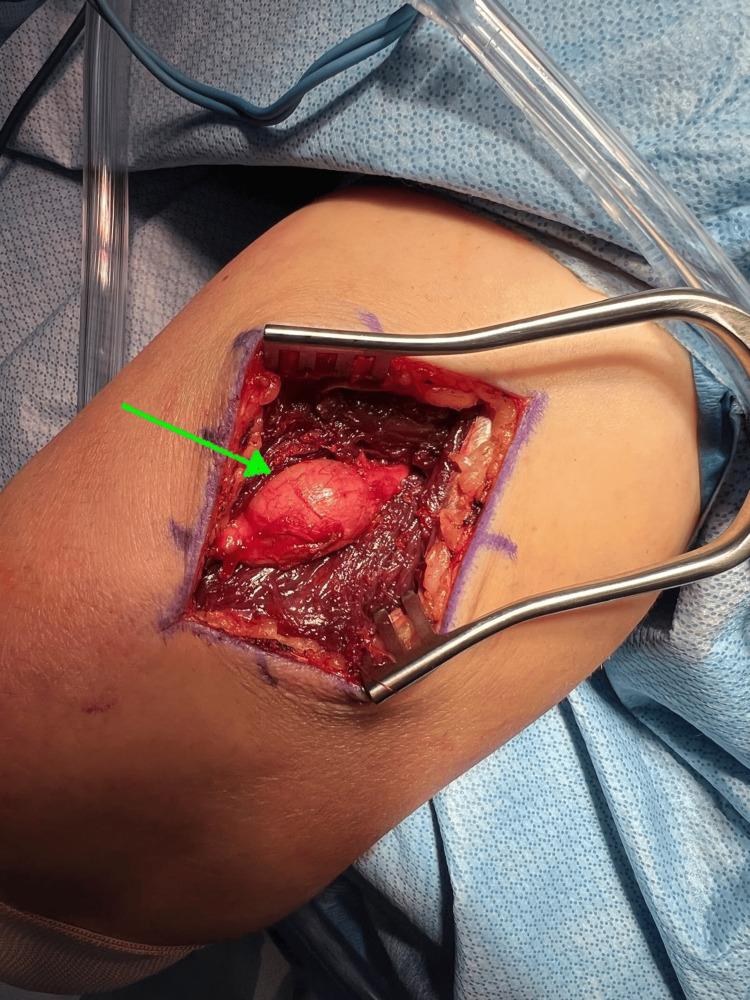

Schwannomas are uncommon, mostly benign nerve sheath tumors that typically present as painless or intermittently painful lumps. They are most commonly found on the flexor surfaces of the body, with occurrence in the radial nerve being exceptionally rare. We present the case of a 55-year-old male with a five-month history of a progressively enlarging, mobile mass on the posterior aspect of the right arm. The patient presented with a transient, "shock-like pain" that failed to respond to conservative management. Imaging confirmed a peripheral nerve schwannoma located deep in the triceps posterior fascia along the lateral head of the triceps within the radial nerve. Due to persistent symptoms and failure of conservative treatment, surgical excision of the neural tumor was recommended. This case highlights the clinical presentation and surgical management of a rare radial nerve schwannoma.

神经鞘瘤并不常见,大多为良性神经鞘膜肿瘤,通常表现为无痛或间歇性疼痛的肿块。它们最常见于身体的屈侧表面,在桡神经中出现极为罕见。我们报告一例55岁男性患者,其右臂后侧有一个进行性增大的可移动肿块,病史长达五个月。患者出现短暂的“电击样疼痛”,保守治疗无效。影像学检查证实为外周神经鞘瘤,位于桡神经内肱三头肌外侧头沿肱三头肌后筋膜深处。由于症状持续且保守治疗失败,建议手术切除神经肿瘤。本病例突出了罕见的桡神经鞘瘤的临床表现及手术治疗。